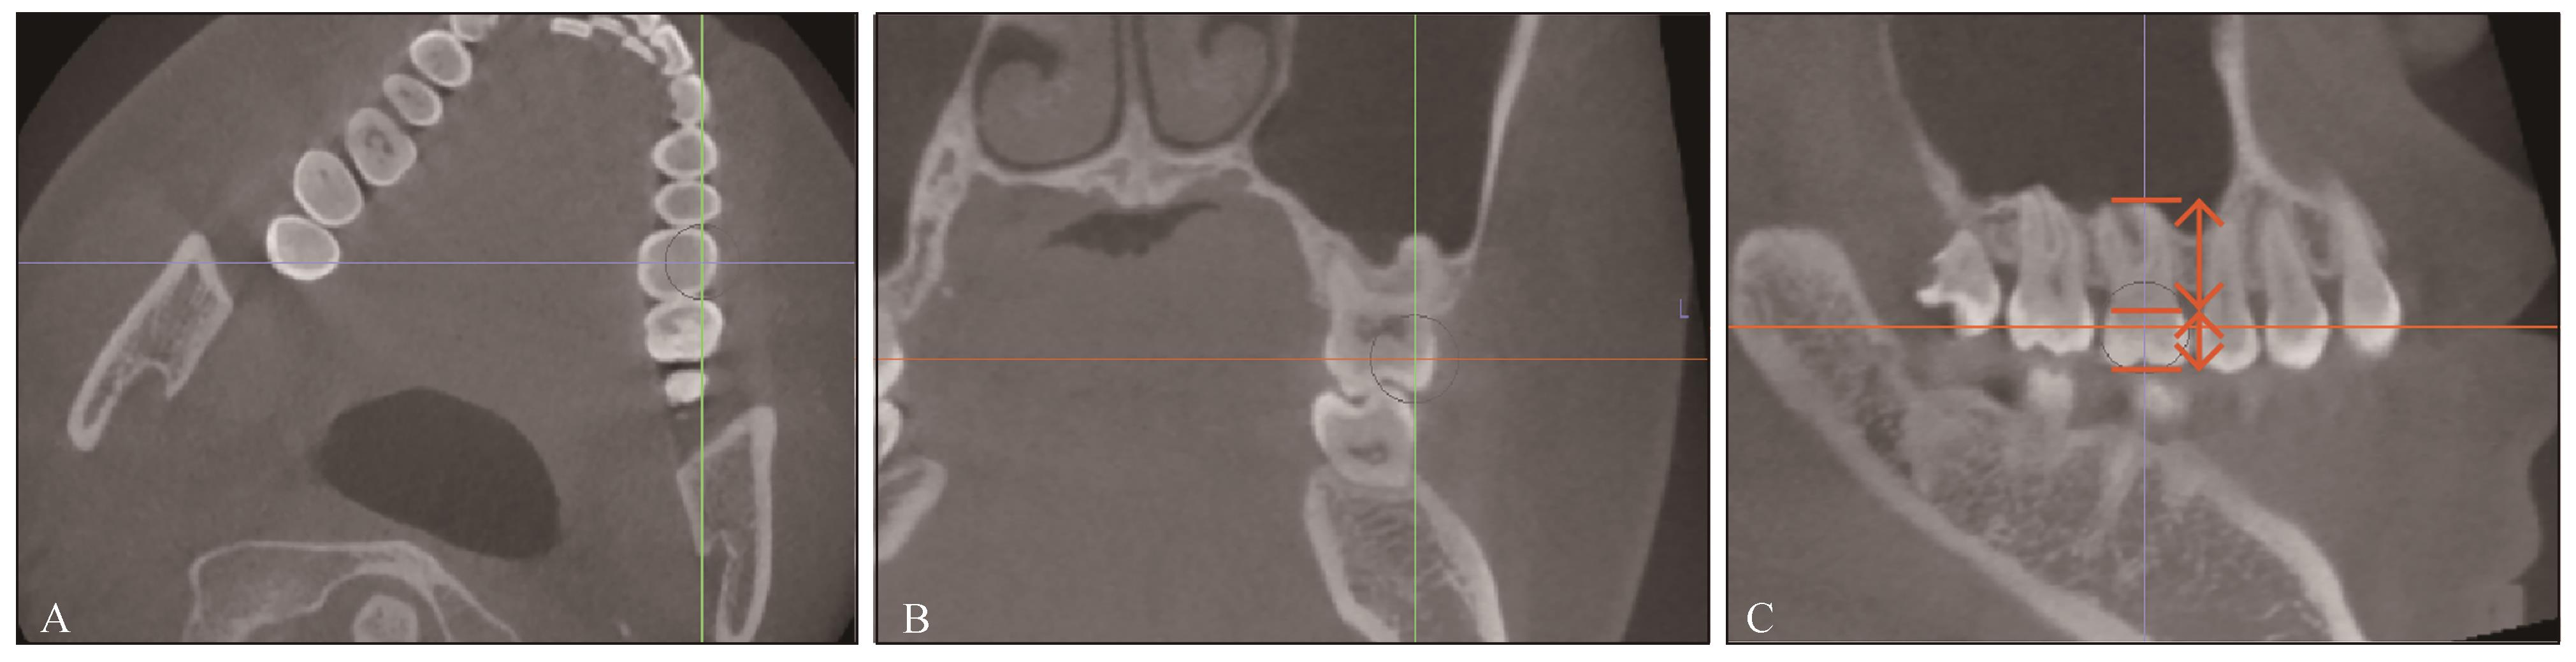

图 1

使用Invivo测量上颌第一磨牙牙冠长度和牙根长度A:从横断面摆正第一磨牙位置;B:从冠状面确定近中颊尖和近中颊根的位置;C:从矢状面测量第一磨牙的牙根长度和牙冠长度(牙根长度:长箭头,从釉牙骨质界到近中根尖;牙冠长度:短箭头,从釉牙骨质界到近中颊尖)。"